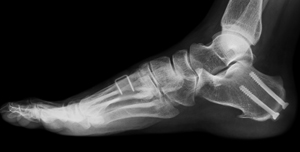

Cavus foot reconstruction is a deformity correction surgery to treat cavus foot which is also called pes cavus or high arches. Cavus foot occurs when the arch on the bottom of the foot that runs from the toes to the heel is arched more than normal. This causes pain and instability in the foot while walking, standing, and running. Cavus foot reconstruction aims to correct the bone shape, its malalignment, muscle imbalance, and foot and ankle instability.

The goal of cavus foot reconstruction is to bring the high arch to a normal position so that it touches the ground, called a plantigrade foot. In addition, the surgeon ensures that the foot and ankle joint is preserved as much as possible without significant loss of bone and muscle tissue. Since it is a foot deformity, structural alterations are made in the foot by cutting and reshaping the bones called an osteotomy. Correction surgery may also include tendon release and bone fusion.

- Your doctor may also perform radiographic exams such as X-ray’s to get a detailed view of the foot and ankle joint to help plan the surgery.